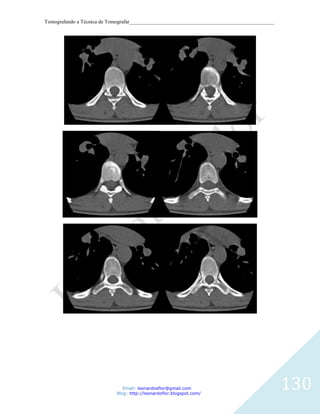

CORTES AXIAIS DAS ORBITAS